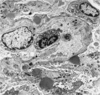

What is this?

glomerulus

E: endothelium

F: fenestration

C: capillary

BM: basement membrane

P2: secondary podocyte process

FS: filtration slit